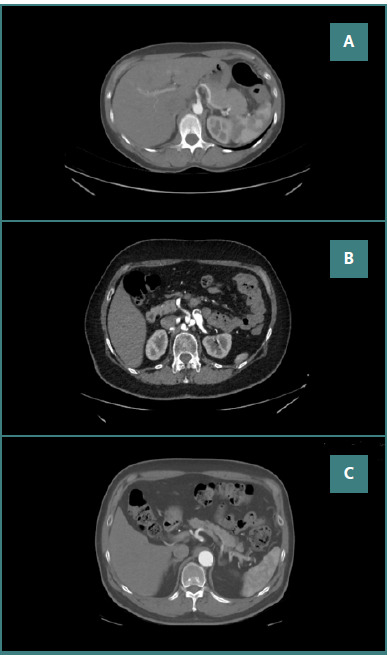

腹腔神经节是一个神经纤维网络,调节与消化有关的各种功能,而腹腔干是一条大动脉,向胃、小肠和上腹部的其他器官供应含氧血液。这些结构的解剖变异是常见的,并且可以对外科和医疗程序产生重大影响。这项前瞻性观察性研究进行了一年多,纳入了300名有外周动脉疾病史的患者(年龄45-75岁),在罗马尼亚布加勒斯特Carol Davila中央军事急救医院使用飞利浦光谱CT 7500进行评估。该研究确定了腹腔干的三种主要解剖变异,每种变异都与腹腔神经节的不同位置分布有关。在腹腔干表现为肝脾干,左胃动脉起源于腹主动脉的病例中,腹腔神经节的外侧位置最为普遍。当肝脾干包括由脾动脉产生的胃左动脉时,最常观察到腹腔神经节的后外侧位置。在肝胃干患者中,脾动脉起源于肠系膜上动脉,腹腔神经节的外侧位置也是最常见的。统计分析显示t统计量分别为7.391和11.319,P值为0.002。本文综述了腹腔神经节的解剖变异及其解剖变异,强调了它们的患病率、临床意义以及对外科和介入性手术的影响。

The celiac ganglia are a network of nerve fibers that regulate various functions related to digestion, while the celiac trunk is a major artery that supplies oxygenated blood to the stomach, small intestine, and other organs in the upper abdominal region. Anatomical variants of these structures are common and can have significant implications for surgical and medical procedures. This prospective observational study was conducted over one year and included 300 patients (aged 45-75 years) with a history of peripheral arterial disease, evaluated at Dr. Carol Davila Central Military Emergency Hospital Bucharest, Romania, using a Philips Spectral CT 7500. The study identified three major anatomical variants of the celiac trunk, each associated with different positional distributions of the celiac ganglia. In cases where the celiac trunk presented as a hepatosplenic trunk with the left gastric artery originating from the abdominal aorta, the lateral position of the celiac ganglia was most prevalent. When the hepatosplenic trunk included the left gastric artery arising from the splenic artery, the postero-lateral position of the celiac ganglia was the most frequently observed. In patients with a hepatogastric trunk, where the splenic artery originated from the superior mesenteric artery, the lateral position of the celiac ganglia was again the most common. Statistical analysis reveals a t-statistic of 7.391 and 11.319 with a P value of 0.002. This article reviewed the anatomical variants of the celiac ganglia and their anatomical variants, highlighting their prevalence, clinical significance, and implications for surgical and interventional procedures.